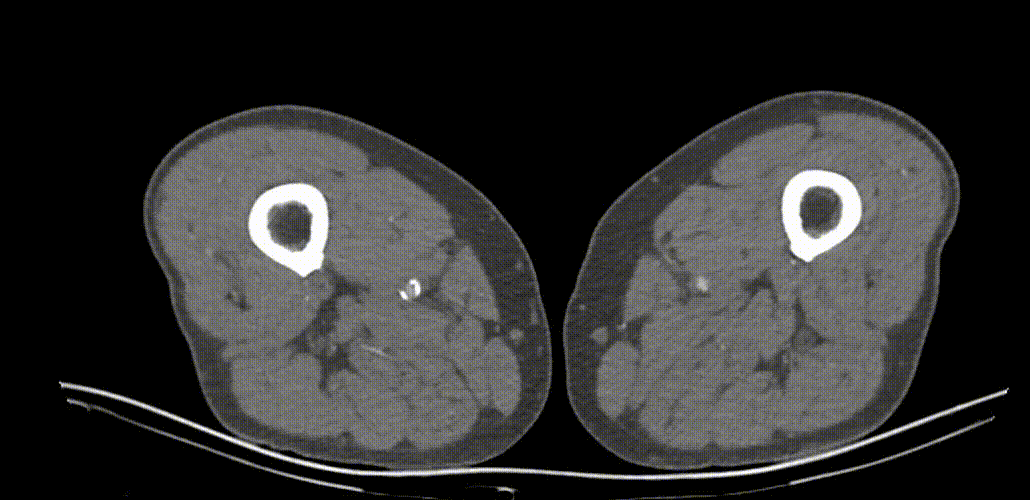

因患者股浅动脉及腘动脉狭窄闭塞段均严重钙化,选择使用振波球囊(6mm*80mm、5mm*80mm)

分别对股浅动脉、腘动脉狭窄闭塞段扩张(球囊至4atm,3级振波强度3个循环,5级振波强度3个循环);球囊切迹逐渐消失

IVUS提示病变段仍有局部重度狭窄,遂选择最新上市的”始祖鸟”紫杉醇药物涂层球囊(5*150mm、6*150mm )对残余狭窄进行扩张

IVUS提示病变段仍有局部重度狭窄,遂选择最新上市的”始祖鸟”紫杉醇药物涂层球囊(6*150mm、 5*150mm ) 分别对股浅动脉、腘动脉、胫腓干动脉逐段扩张,压力至工作压维持3分钟。